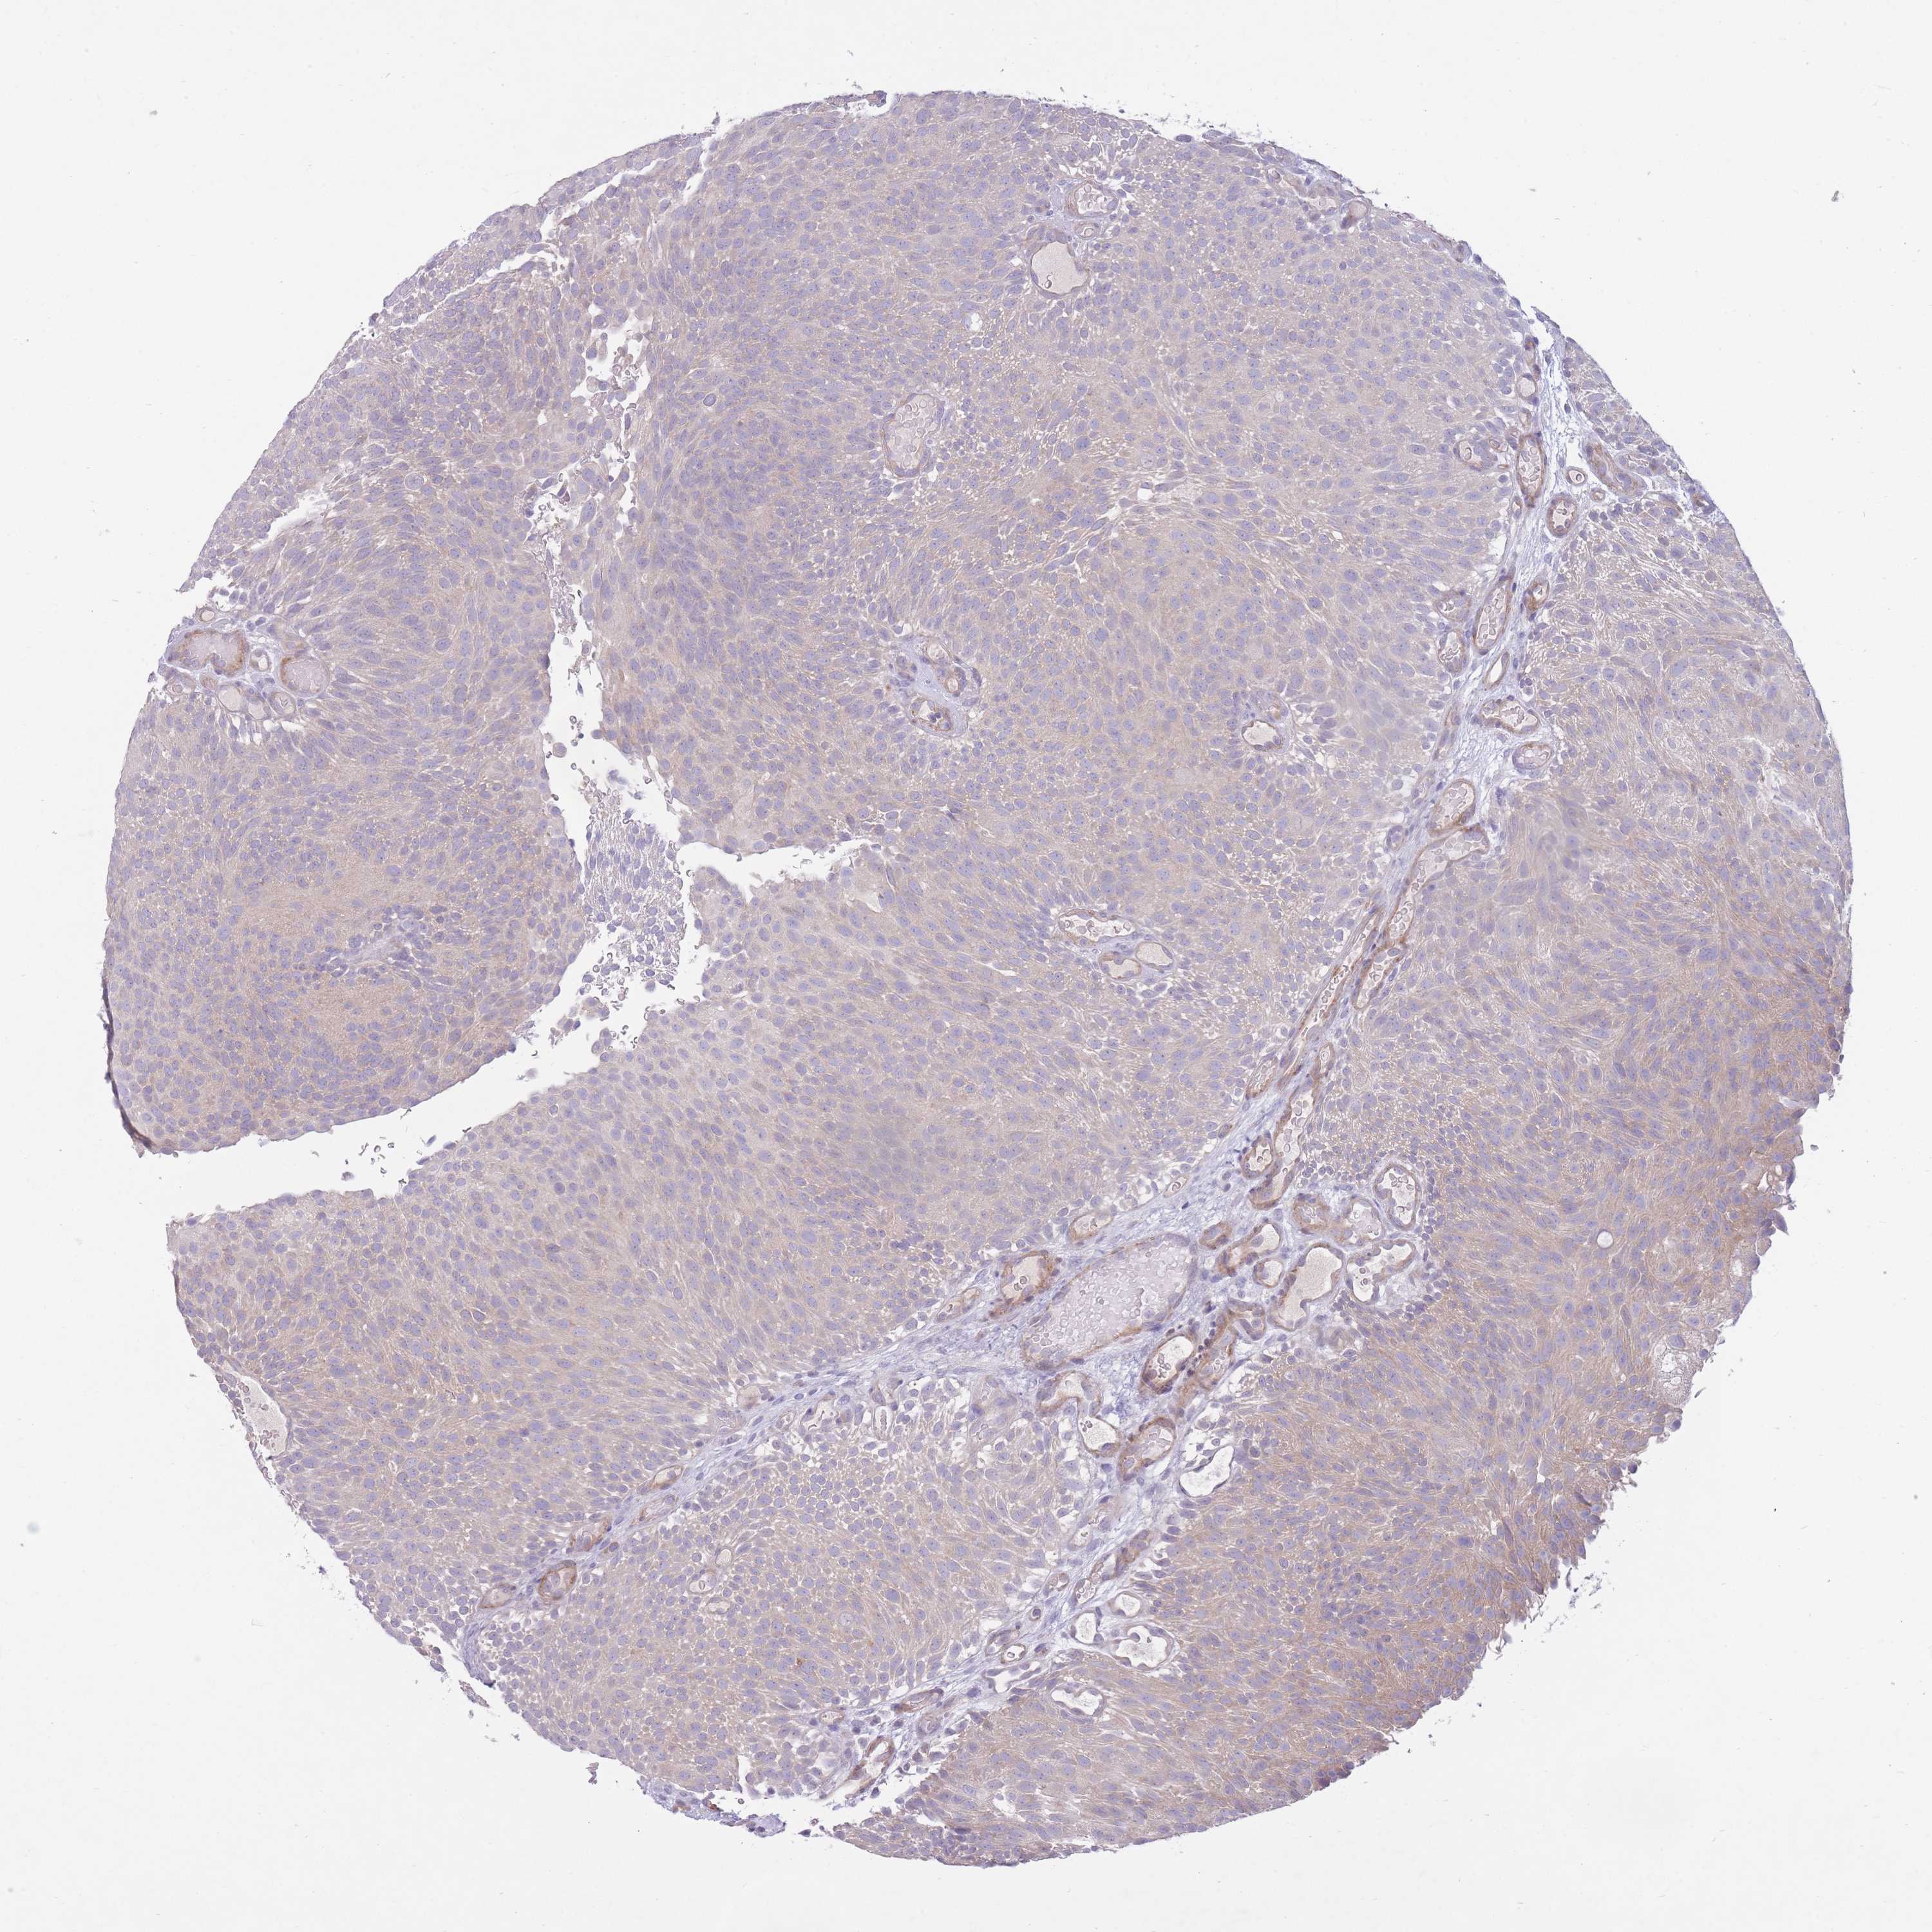

UROTHELIAL CANCER - Protein expressioni

A mouse-over function shows sample information and annotation data. Click on an image to view it in a full screen mode. Samples can be filtered based on level of antibody staining by selecting one or several of the following categories: high, medium, low and not detected. The assay and annotation is described here.

Note that samples used for immunohistochemistry by the Human Protein Atlas do not correspond to samples in the TCGA dataset.

Antibody stainingi

Antibody staining in the annotated cell types in the current human tissue is reported as not detected, low, medium, or high, based on conventional immunohistochemistry profiling in selected tissues. This score is based on the combination of the staining intensity and fraction of stained cells.

Each image is clickable and will lead to virtual microscopy that enables deeper exploration of all samples and also displays staining intensity scores, fraction scores and subcellular localization as well as patient and tissue information for each sample.

Antibody HPA050409

Antibody HPA054211

Urothelial carcinoma, Low grade

Urothelial carcinoma, High grade

Urothelial carcinoma, NOS